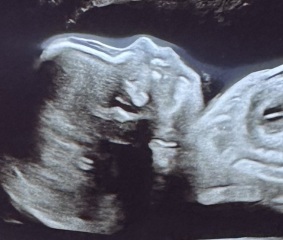

Can anyone see any fluid on my babies brain? I went for a private 4D ultrasound and they did a growth scan too, they said my baby had a slightly bigger head than average (98th percentile!!!!) and I've been googling..... she didn't mention any abnormalities.